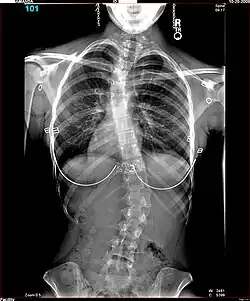

Lateral curvature of the spine in a scoliosis patient

The Harrington Rod, or Harrington implant, is a device for the straightening of the spine inside the body, designed by Paul Harrington. The device consists of a stainless steel rod, attached to the spine at the top and bottom of the curve with hooks. Attached ratchets are then tightened to distract or straighten the spine. Following surgery to insert the rod, the patient wears a postoperative plaster cast or brace for a few months, until vertebral fusion has occurred, after which the cast or brace is removed.[5]